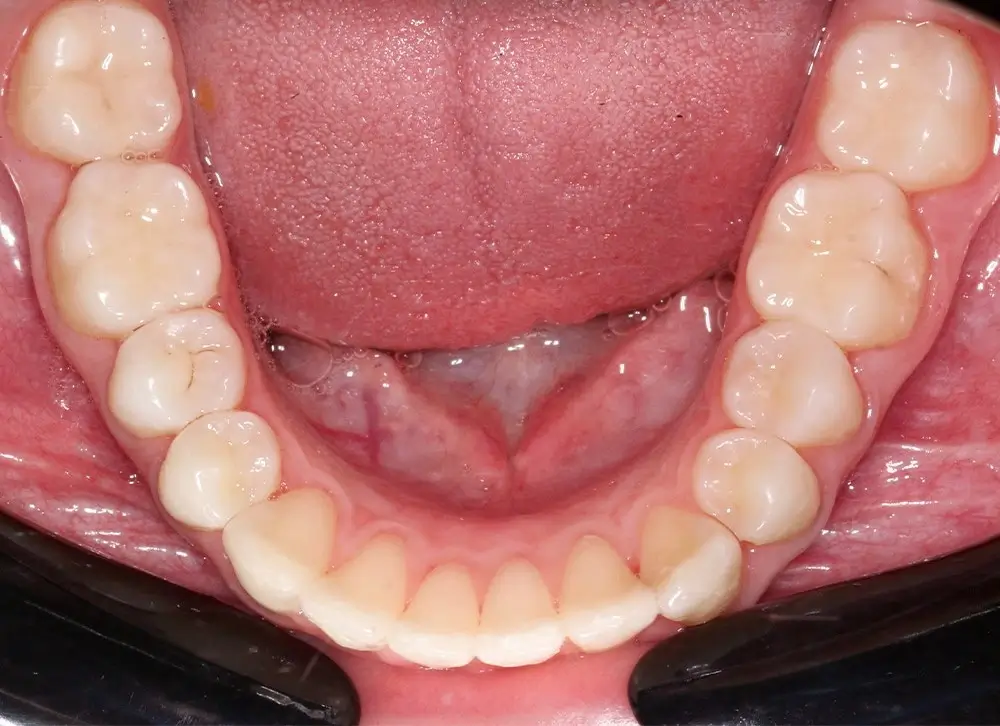

Скученность - Кейс 10

Эффективность устранения дефекта прикуса посредством элайнеров FlexiLigner.

16

Количество кап НЧ

Количество кап ВЧ

Результаты лечения